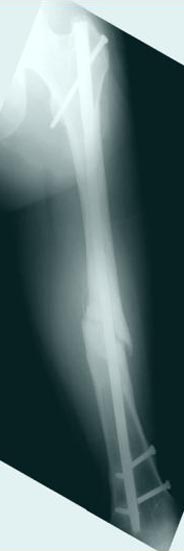

Лечение бедра - ургентное оперативное лечение антеградным с минимально рассверливанием, фиксацией с минимальным диаметром штифта и плюс irrigation and debridment и с закрытием поперечной до 10 см раны на уровне перелома в день поступления.

Снимки представлены: 1 мес; 3 мес; 1 год; 2 года, предоперационные и ротационная КТ грамма

Аппарат Илизарова= Taylor spatial frame

Операцию провели в два этапа, сперва удалили штифт, рассверливание римером на пару мм большего диаметра, определение чувствительности на анаэробную и аэробную культуру (где исследования показали негативный результат чувствительности), через дней десять - начали аппаратную фиксацию.